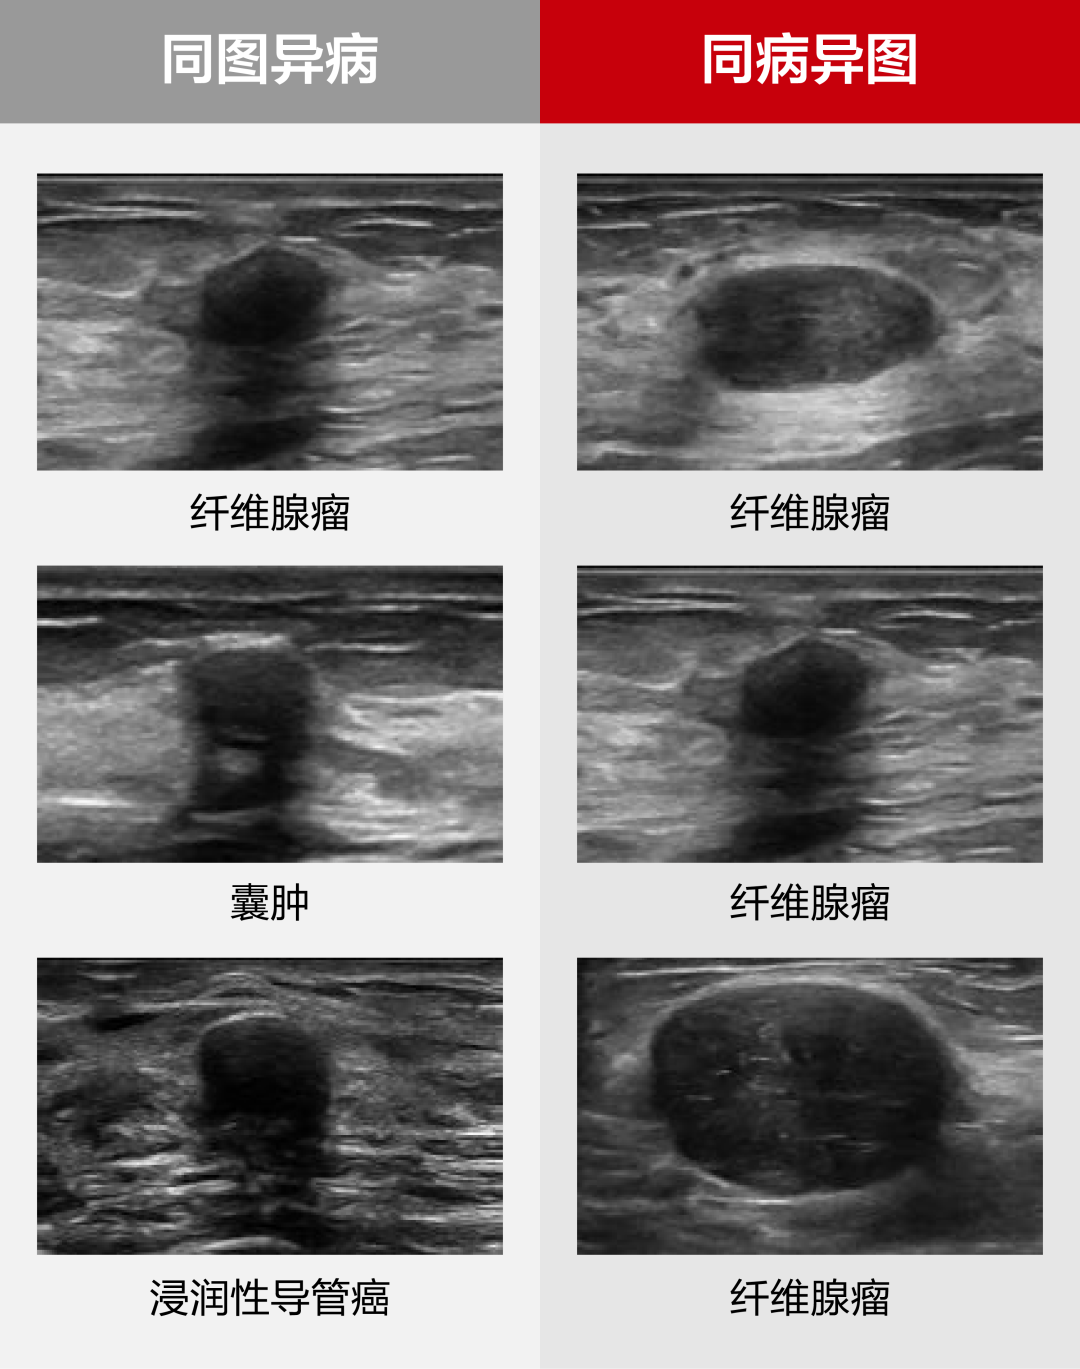

然而,单切面二维图像的局限性、病例表征的非特异性、恶性肿瘤的隐匿表征,以及超声经验积累周期长等问题,成为全球超声医学发展亟待解决的难点。乳腺病灶的精准诊断评估在临床上仍面临巨大挑战,尤其困扰经验较缺乏的年轻超声医生。